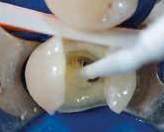

L'isolamento del campo operatorio, tramite diga di gomma, è una condizione imprescindibile per poter operare in condizioni ottimali ed in massima sicurezza.

La preparazione dell’accesso canalare (flaring)

Un passaggio fondamentale che precede la preparazione canalare consiste nell’apertura e ampliamento della camera pulpare. Un adeguato ampliamento consente una completa visione del pavimento e degli imbocchi canalari.

Per conseguire una sagomatura che rispetti l’anatomia originale, occorre eliminare le interferenze coronali (triangolo dentinale) in modo che gli strumenti endodontici possano essere inseriti con una traiettoria quanto più possibile in linea con l’asse del canale.

Lo strumento Absolute Access permette di eseguire questo passaggio nel modo più appropriato. Dopo aver eseguito lo scouting, si inizia a preparare l’imbocco del canale utilizzando lo strumento e lo si introduce fino al terzo coronale, prima di eventuali curvature, con movimenti circonferenziali di brushing, in appoggio alle pareti, evitando di ingaggiare la punta dello strumento ed il potenziale avvitamento.